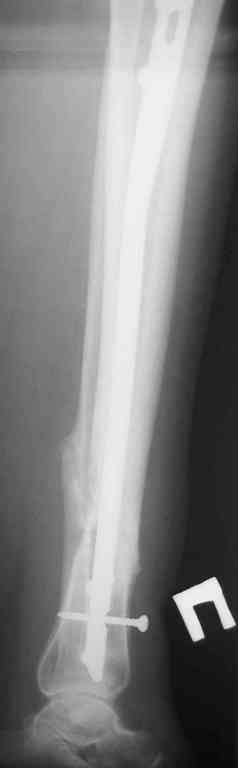

Re: Ложный сустав голени перелом штифта

послал В. Машталов 23 Октябрь 2007, 12:09

Прилагаются.